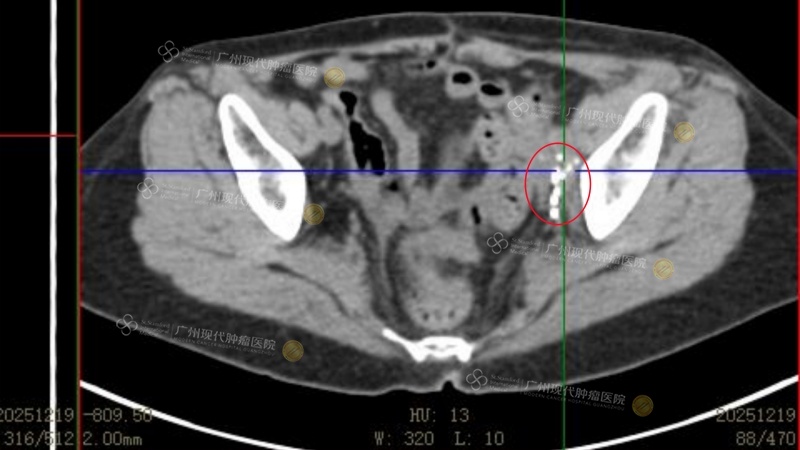

(4次治疗后,2025年12月19日复查显示肿瘤基本完全失活)

疗效立竿见影:第一次治疗结束后,折磨她许久的腹痛就消失了。第二次治疗后,腿部血液循环恢复,左腿肿胀明显消退。“这给了我巨大的信心,”符爱琴兴奋地分享道,“第四次治疗结束做了pet scan,真的能看到肿瘤明显萎缩了。”历时三个月,截至目前,符爱琴的盆腔淋巴结基本完全失活,肝脏肿瘤消失不见,整体疗效评估可达到PR。